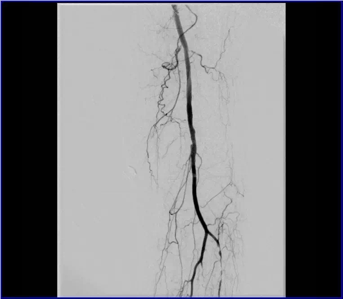

動脈閉塞處支架植入

血管內(nèi)微創(chuàng)介入治療(球囊擴張、支架植入)是國際上治療下肢動脈缺血疾病最常用、首選的一種微創(chuàng)、安全、高效的治療方法。